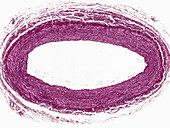

13613516 - Vein adventitia, light micrograph

13613519 - Layers of a large vein wall, light micrograph

13613518 - Layers of a large vein wall, light micrograph

13613504 - Muscular artery, light micrograph

13613513 - Large vein, light micrograph

13613521 - Large vein wall, light micrograph

13613514 - Large vein wall, light micrograph

13613522 - Large vein wall, light micrograph

13613515 - Large vein wall, light micrograph

13613523 - Large vein wall, light micrograph

13613517 - Layers of a large vein wall, light micrograph